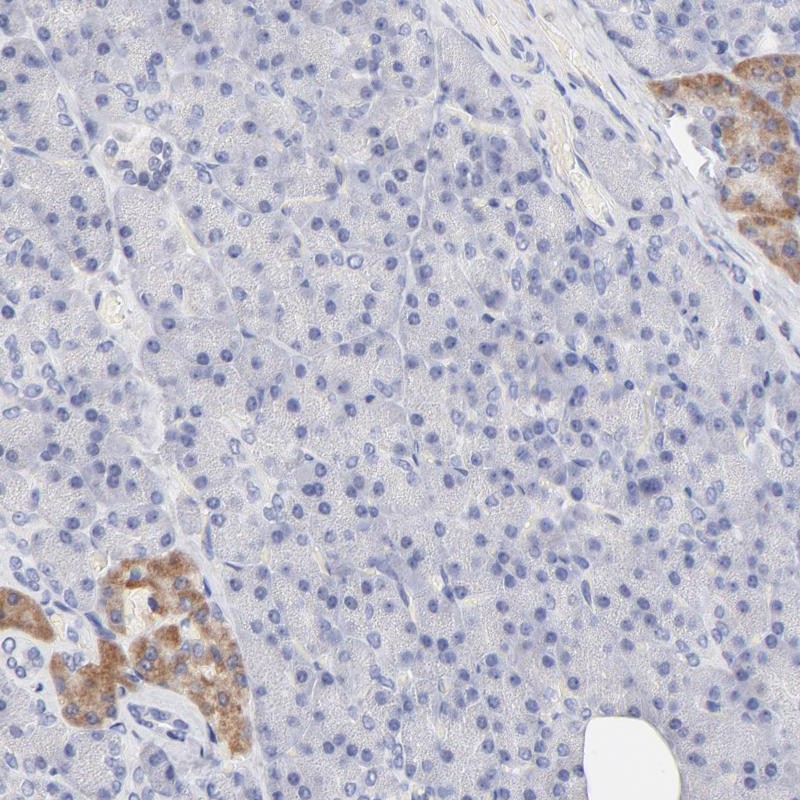

Immunohistochemical staining of human pancreas shows cytoplasmic positivity in islet cells.